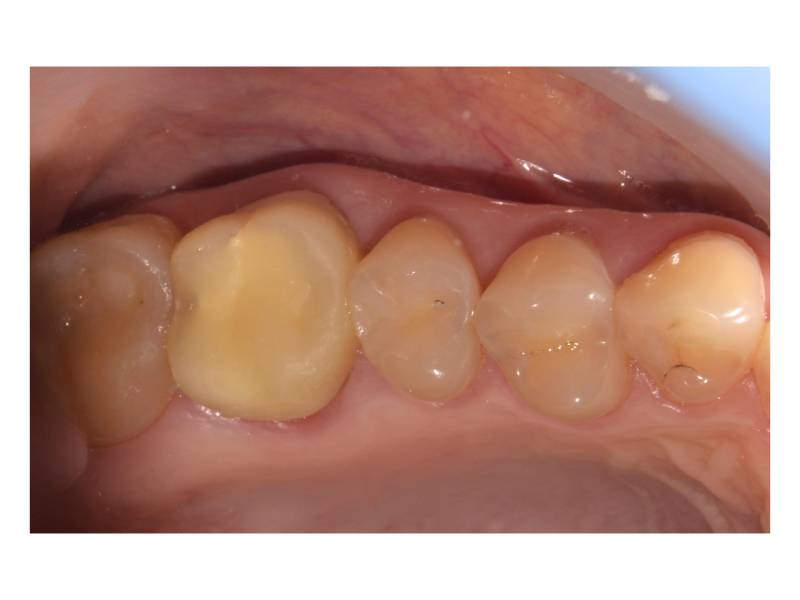

Установка коронки на зуб

Девушка, 28 лет, обратилась после удаления зуба, с целью установки импланта на его место. Задача — создать зуб белее естественного оттенка, чтобы соответствовать планируемому отбеливанию всей зубной линии. Установлен имплант в область удалённого зуба. Зуб сделан белее, чем естественные зубы, с учётом будущего отбеливания. Проведены 2 посещения, срок реабилитации

Доктор: Нурисламов Фадис Фирдависович